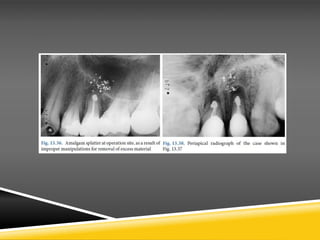

• Splattering of amalgam at the operation site, due to inadequate apical isolation

and improper manipulations for removal of excess filling material

• Staining ofmucosa due to amalgamthat remained at the surgical field (amalgam

tattoo) (Healing disturbances, if the semilunar incision is made over the bony